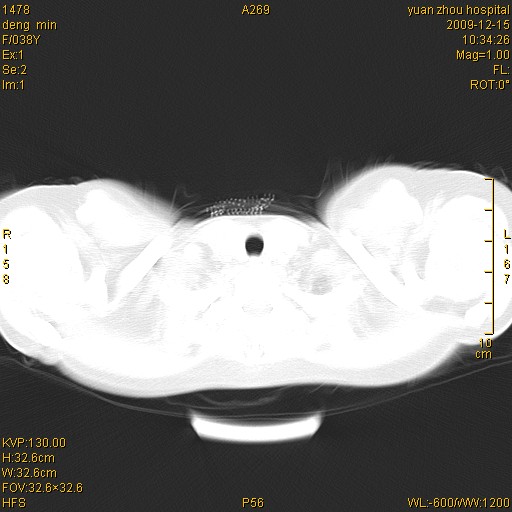

标题: CT23919:F38Y 咳嗽月余 [打印本页]

标题: CT23919:F38Y 咳嗽月余

右肺中下叶、左肺上叶舌段及左肺下叶支气管扩张合并感染。